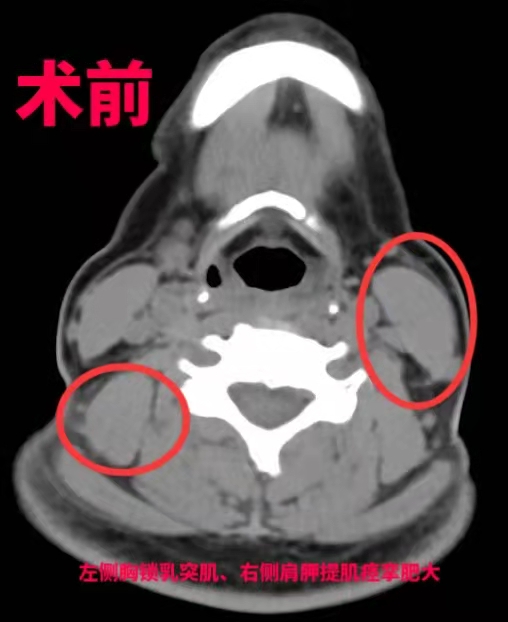

导致痉挛性斜颈作用的原理是比较清晰的,大就是被部分神经控制的肌肉群过于亢奋和紧张。在不能损毁肌肉导致大面积创伤的情况下,通过神经外科手术离断关键的支配神经的神经根,就能缓解肌肉群的过度亢奋。

“最好的方式是手术,考虑到钟女士年轻还要负担一家老小,我们决定选择用‘超选择性神经根切断术’治疗她的痉挛性斜颈。”王向宇表示,相比于其他方式,这种术式需要在术前进行详细检查和评估,通过影像、肌电图检查、选择性肌肉阻滞等专业方法,事先找到“肇事”肌肉,在术中用最小电量反复刺激,精准找到这些“肇事”肌肉的支配神经,进行选择性的神经根切断,而不伤害其他神经和肌肉,进一步减少损伤。经过6个小时后,手术宣布成功,钟女士经过1周的恢复,“歪脖子”的问题得到了根本性解决。

而传统的选择性神经根切断术,往往会导致神经切断过多或切断不完全,切断神经也就意味着失去了部分的神经支配功能,且这种损伤是无法恢复的,一旦切断过多容易引起声音嘶哑、喝水呛咳、肩膀无力等并发症。